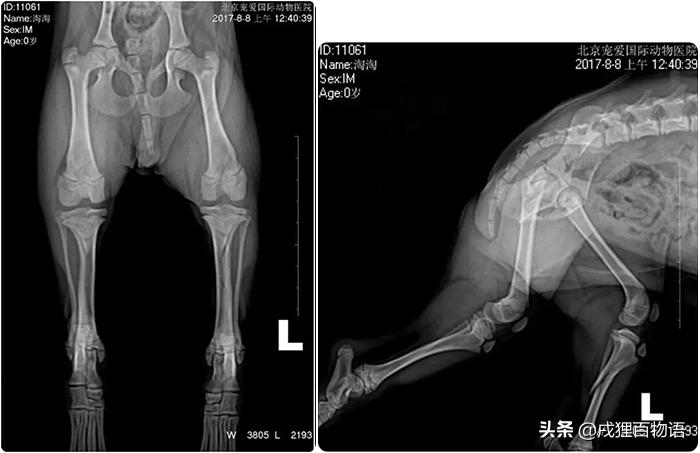

化验:DR显示左后肢不完全骨折

左后肢胫骨不完全骨折